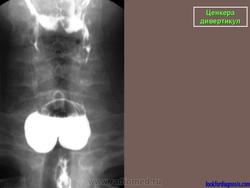

Ценкера дивертикул.

Barium swallow with fluoroscopy, lateral view</p> <p>During swallowing an outpouching of the posterior hypopharyngeal wall is clearly visualised at the level C5-C6, right above the upper oesophageal sphincter. The pouch is characterized by a narrow neck entrapping some barium after the swallowing.

ID: 12377 Zenker's diverticulum Dr Erik Ranschaert - 18 Nov 2010 Zenker's diverticulum

Zenker's diverticulum AP </p> <p>

ID: 13718 Zenkers diverticulum Dr Lee-Anne Slater - 10 May 2011 Barium swallow showed a large posterolateral pouch just above the level ...